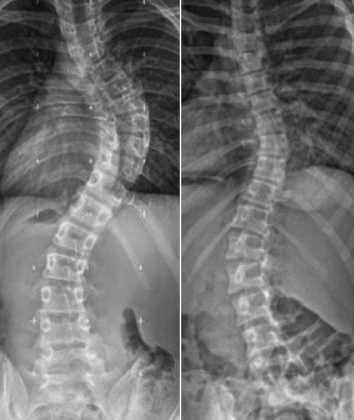

يعاني الكثير من الأطفال والمراهقين من اعوجاج العمود الفقري (الجنف)، ويُلاحظ أن القدرة على تصحيح الانحناء تقل كلما اقترب الطفل من سن نضج العظام. السؤال الذي يطرحه كثير من الأهل: لماذا يصبح الظهر أقل مرونة مع مرور الوقت، وكيف يؤثر ذلك على العلاج؟ هذا المقال يشرح الموضوع بطريقة سهلة وبسيطة للأهل والمراهقين.

خلال النمو السريع، يكون العمود الفقري مرنًا وقابلًا للتعديل. هذا يمنح فرصة كبيرة لحزام اعوجاج العمود الفقري أو التمارين العلاجية لتصحيح الانحناء تدريجيًا.

المرونة تقل تدريجيًا مع النمو، وليست عملية مفاجئة. تبدأ مرحلة فقدان المرونة خلال فترة النمو السريع، وهي أفضل فرصة لتصحيح الانحناء. إذا اكتُشف الجنف مبكرًا وتم البدء بالعلاج المناسب بالحزام أو التمارين العلاجية، تكون النتائج أفضل بكثير.

مع وصول نهاية مرحلة المراهقة، تقل مرونة العمود الفقري بشكل كبير، ويصبح تصحيح الانحناء صعبًا.